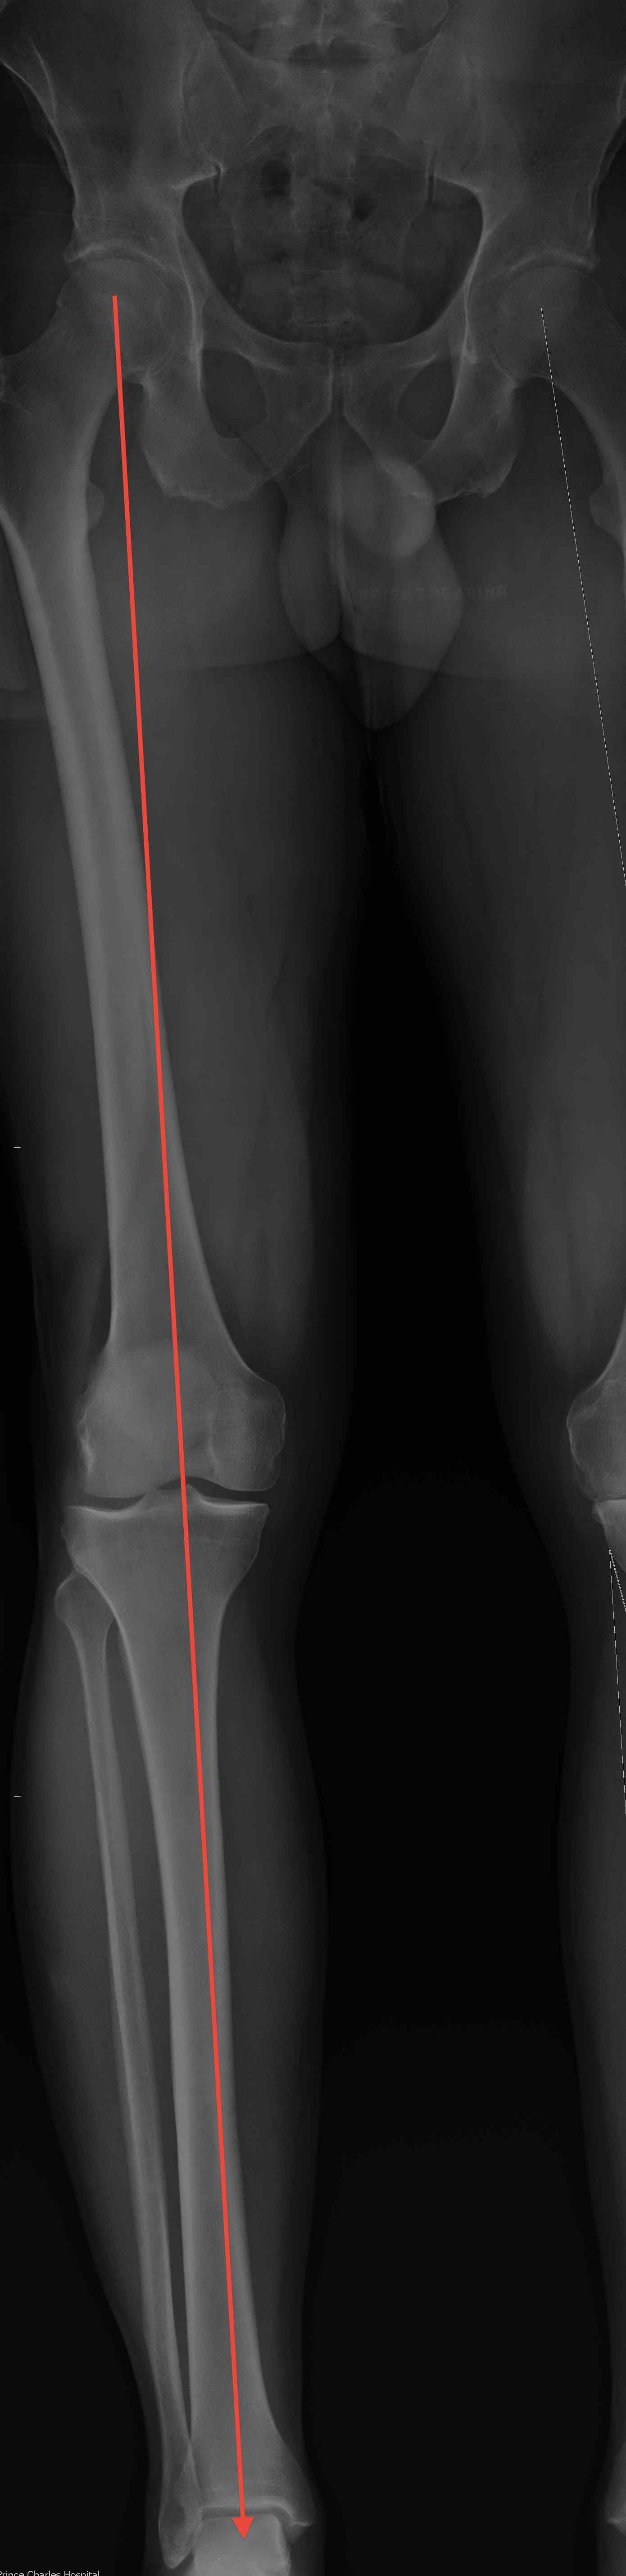

Mechanical Femorotibial axis

- centre of femoral head to medial tibial spine

- medial tibial spine to centre ankle

- should be a straight line 180o +/- 3o